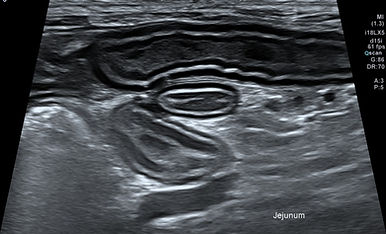

초음파

Ultrasound / Echocardiography

초음파 검사는 신체에 무해한 고주파 음파를 이용해 내부 장기와 조직을 실시간으로 영상화하여 관찰하는 비침습적 진단 검사입니다.

복부초음파

Abdominal Ultrasound

복강 장기 (간, 담낭, 비장, 신장, 부신, 방광, 위장관, 췌장, 생식기계 등) 실질의 이상 소견과 혈관 이상을 평가할 수 있으며,

혈액 검사 및 방사선 검사만으로는 명확히 확인되지 않는 각종 질환에 대한 감별에 유리합니다.

또한, 초음파 유도 하에 안전하게 세침흡인검사 및 복수/흉수/심낭수 천자가 가능합니다.

본원에서는 환자의 안정을 최우선으로 하여, 숙련된 영상 전공 수의사가 조용하고 독립된 검사실에서 세심하게 검사를 진행합니다.

위종양

만성신장질환

방광염

장염

자궁수종